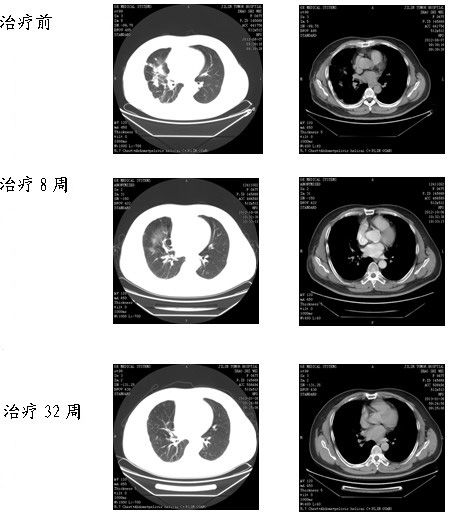

临床诊断:右肺下叶背段及中叶中分化腺癌楔形切除术后(cT4N2M1b)Ⅳ期,右胸壁转移活检术后、右肺内转移、纵隔淋巴结转移、右侧胸膜转移。患者符合DACOMITINIB(达克替尼)与厄洛替尼对照2、3线治疗晚期非小细胞肺癌的临床研究的入组标准,经与患者及家属详细沟通,告知参加临床研究可能获益及可能承担风险,患者及家属表示知情,同意参加临床实验,签署知情同意书,入组临床试验,现口服厄洛替尼/安慰剂和PF-00299804/安慰剂每天各一片,8周后复查CT疗效PR,现已口服药物,32周,疗效CR。